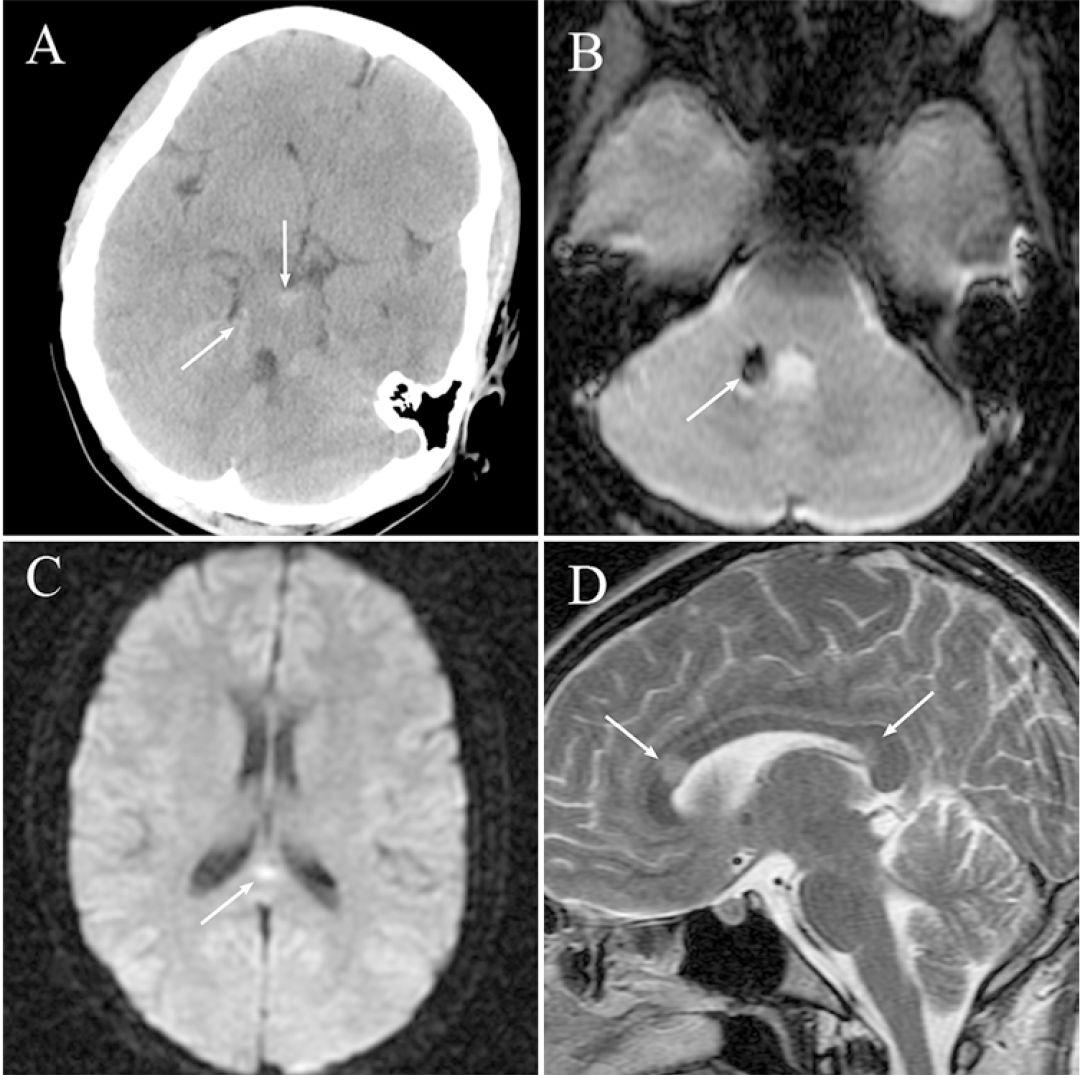

弥漫性轴索损伤 1 例

弥漫性轴索损伤ct表现所见!

病例回顾------弥漫性轴索损伤(diffuse axonal injury,dai)影像学及

车祸伤后昏迷8小时;胼胝体非出血性弥漫性轴索损伤

【病例讨论】弥漫性轴索损伤?有图有真相! [病例帖]

【读片】磁敏感序列(swi)对弥漫性轴索损伤(dai)的诊断 [病例帖]

中线部位tsah提示重型弥漫性轴索损伤